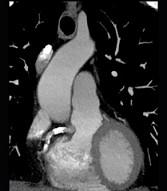

下面一组图像应考虑为 ( )A、左前降支钙化B、左旋支钙化C、正常的左前降支D、右侧冠状动脉钙化E、正常的右侧冠状动脉

问题 下面一组图像应考虑为 ( )

选项 A、左前降支钙化 B、左旋支钙化 C、正常的左前降支 D、右侧冠状动脉钙化 E、正常的右侧冠状动脉

答案 D